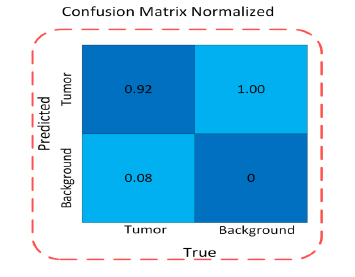

The confusion matrices associated with the suggested YOLOv12 model are graphically depicted in Fig. (6) using the validation data. The normalised confusion matrix is utilized to pinpoint the highest and lowest performing classes, providing a comprehensive understanding of the model's performance across various categories.

YOLOv12 model normalised confusion matrix.